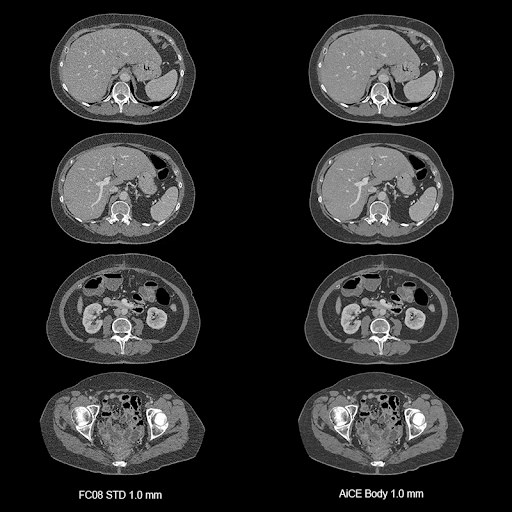

Визуализация органов грудной полости, живота и малого таза